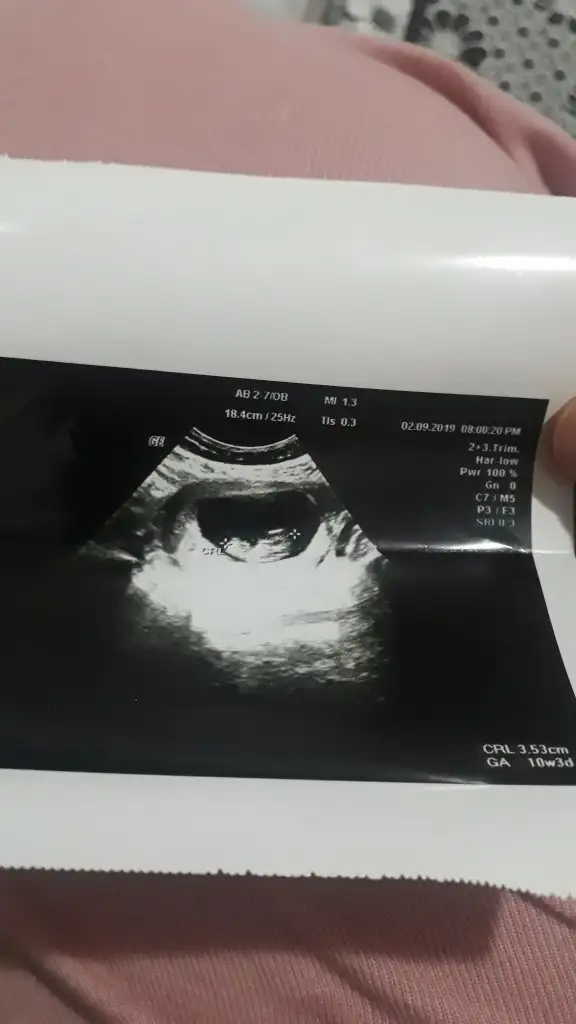

Başka usg varsa paylaşın net degilMerhaba hanımlar 11. Haftadayız bizede bir cinsiyet tahmini yaparmisiniz![]()

Erkek geliyor canım :)Kız 13+ haftadasınız